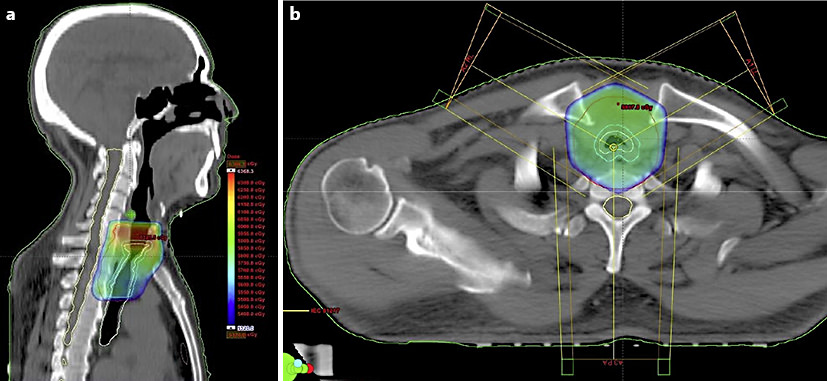

Schedule ConsultationTracheal Adenocarcinoma Treated with Adjuvant Radiation: A Case Report and Literature Review

There are many studies showing the benefit of postoperative irradiation therapy in primary tracheal malignancies such as SCCs and ACCs. However, little experience has been shared in the case of primary adenocarcinomas of the trachea, the tumor type described in our report. The prognosis of patients with malignant tumors of the trachea remains gloomy, and long-term median survival of tracheal adenocarcinoma patients undergoing combined modalities is unknown to us. Primary adenocarcinoma of the trachea needs to be diagnosed at an early stage, and combined multimodal approaches may be explored to attain an extended median survival.